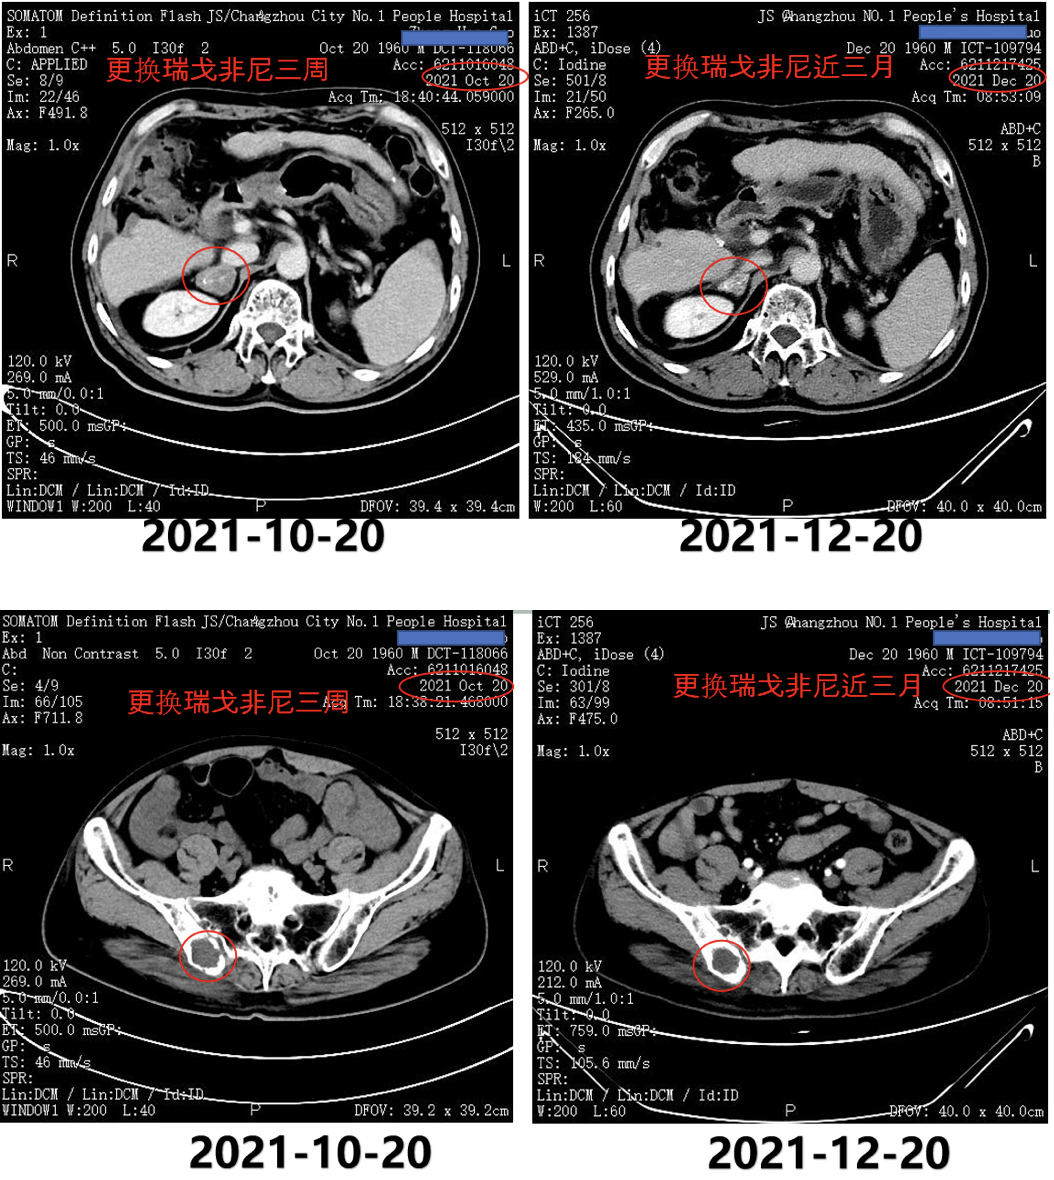

2021年10月18日AFP为443.9ng/ml。2021年10月20日复查CT示,肾上腺病灶较前明显增大,髂骨病灶缩小(图8)。

图8.2021年10月20日复查CT

2021年11月8日、2021年11月29日和2021年12月20日复查AFP分别为421.3ng/ml、255.5ng/ml和286.3ng/ml。

2021年12月20日复查CT示,右侧肾上腺病灶明显缩小,髂骨病灶也进一步缩小(图9)。

图9.2021年12月20日复查CT